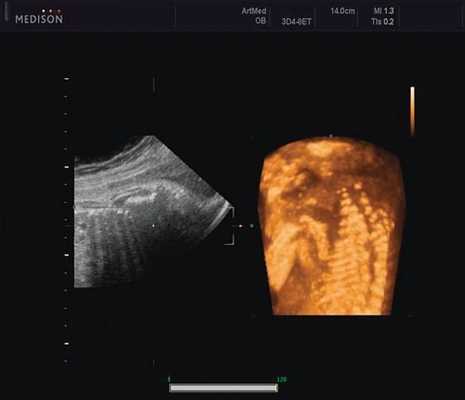

Клиническое наблюдение 1

Пациентка К., 26 лет, обратилась в клинику в 23 нед беременности. Беременность первая. Исследование проводилось на аппарате Accuvix-XQ (Samsung Medison) с использованием режима поверхностной объемной реконструкции 3D/4D. Показатели фетометрии полностью соответствовали сроку беременности. В процессе сканирования позвоночника во фронтальной и сагиттальной плоскостях выявлена угловая деформация позвоночника в грудном отделе, протяженностью около трех позвонков. В поперечной плоскости сканирования нарушения структур и целостности тканей не было обнаружено. В режиме 3D/4D реконструкции было выявлено асимметричное расхождение ребер правой и левой стороны грудной клетки (рис. 4).

Рис. 4. Эхографическая картина асимметрии ребер в режиме 3D реконструкции.

Ребра левой стороны были сближены, межреберные промежутки уменьшены по сравнению с противоположной стороной (рис. 5, 6). Другой патологии у плода не было выявлено. Заподозрен врожденный сколиоз, основой которого является наличие боковых полупозвонков (hemivertebrae) или боковых клиновидных позвонков. В 26 нед ультразвуковая картина сохранялась. При проведении трехмерной эхографии получено отчетливое изображение асимметрии реберных дуг и сколиотическая деформация позвоночника.